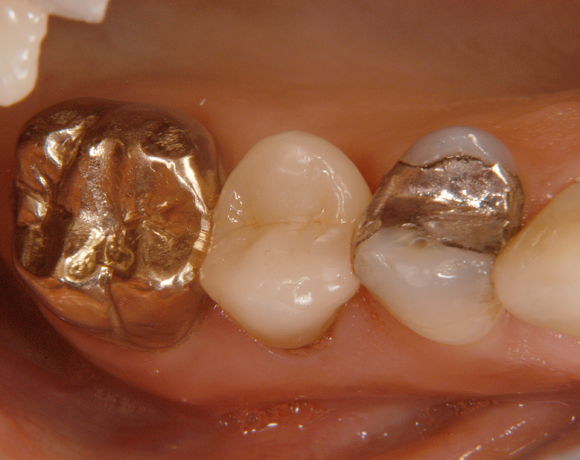

Ein Projekt aus dem Jahr 2003